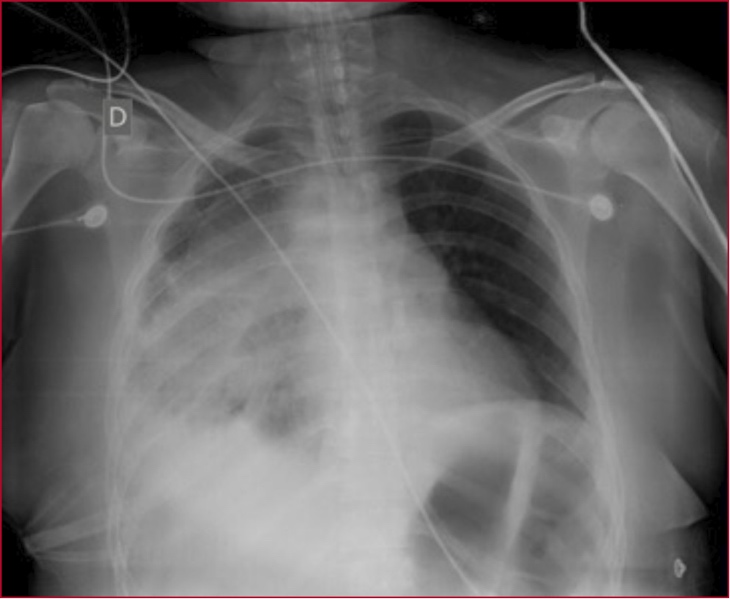

La paciente ingresa en la unidad de terapia intensiva hemodinámicamente inestable, con requerimientos de vasopresores a altas dosis, por lo que se mantiene bajo sedoanalgesia y conectada a asistencia respiratoria mecánica. Se solicita una radiografía de tórax de control (Figura 2).

Figura 2. Radiografía de tórax de control posoperatorio. Se observa radiopacidad en el hemitórax derecho correspondiente a la zona del tumor, con ocupación del ángulo costofrénico debido al derrame pleural asociado.